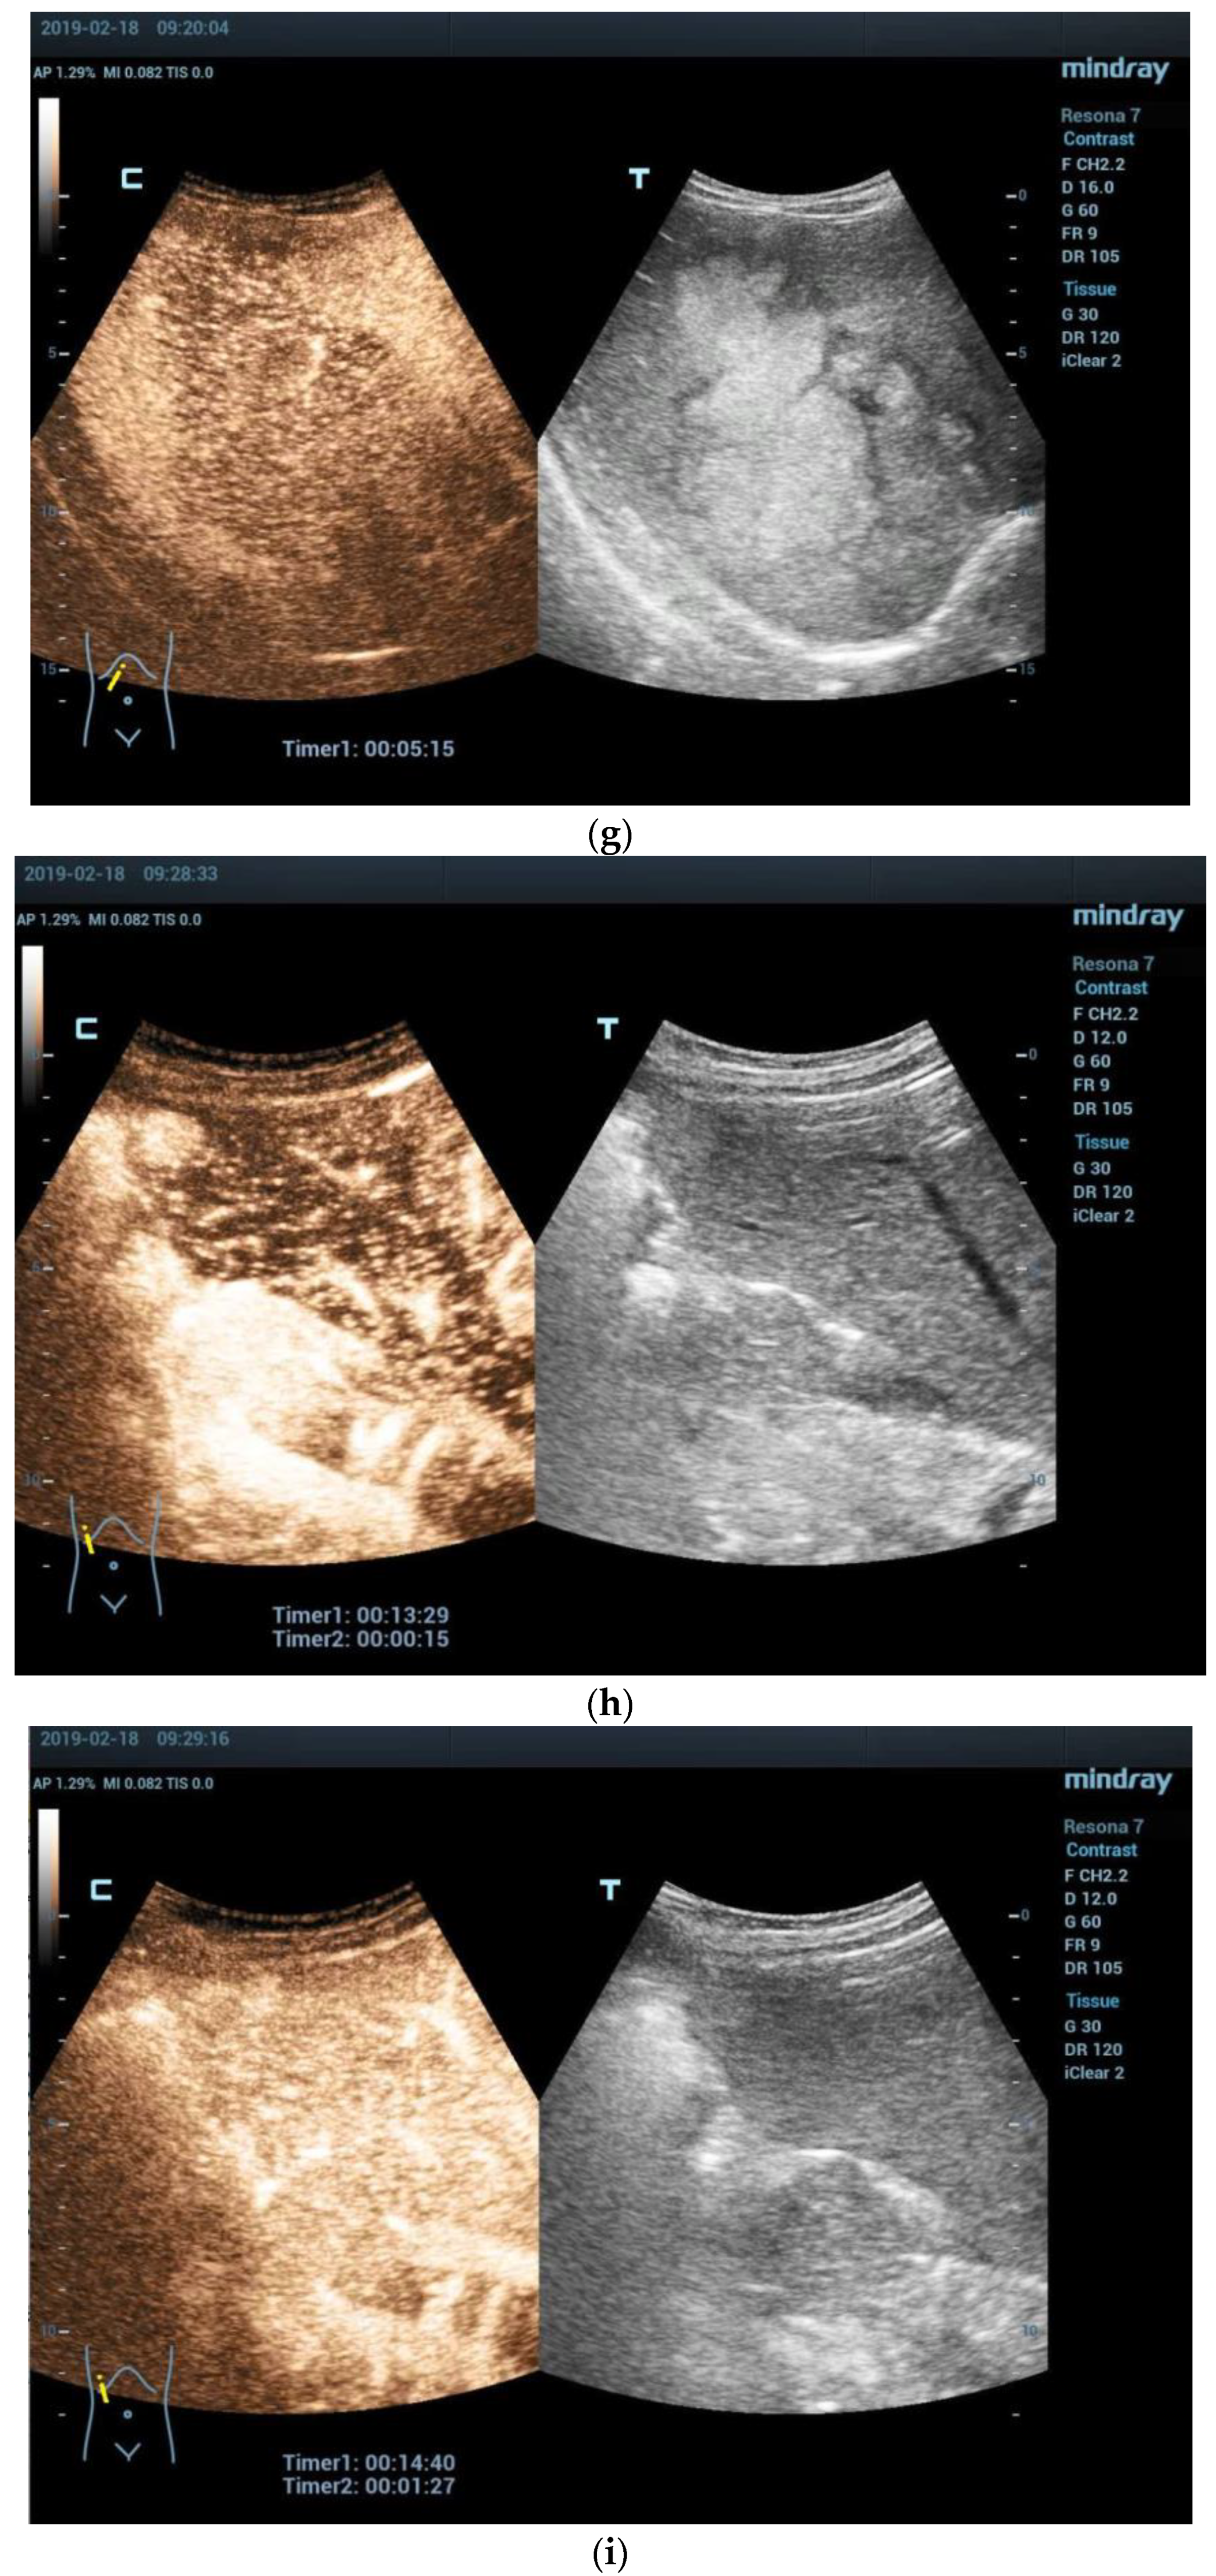

- Anupindi, S.A.; Biko, D.M.; Ntoulia, A.; Poznick, L.; Morgan, T.A.; Darge, K.; Back, S.J. Contrast-enhanced US Assessment of Focal Liver Lesions in Children. Radiographics 2017, 37, 1632–1647. [Google Scholar] [CrossRef]

- Wang, G.; Xie, X.; Chen, H.; Zhong, Z.; Zhou, W.; Jiang, H.; Xie, X.; Zhou, L. Development of a pediatric liver CEUS criterion to classify benign and malignant liver lesions in pediatric patients: A pilot study. Eur. Radiol. 2021, 31, 6747–6757. [Google Scholar] [CrossRef] [PubMed]

- McCarville, M.B. Contrast-enhanced sonography in pediatrics. Pediatr. Radiol. 2011, 41 (Suppl. S1), S238–S242. [Google Scholar] [CrossRef] [PubMed]

- Dong, Y.; Wang, W.P.; Mao, F.; Zhang, Q.; Yang, D.; Tannapfel, A.; Meloni, M.F.; Neye, H.; Clevert, D.A.; Dietrich, C.F. Imaging Features of Fibrolamellar Hepatocellular Carcinoma with Contrast-Enhanced Ultrasound. Ultraschall Der Med. 2021, 42, 306–313. [Google Scholar] [CrossRef] [PubMed]